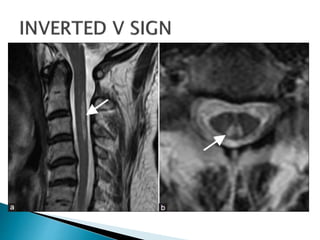

 MRI SPINE –hyperintense T2 WEIGHTED signal

in posterior and anterolateral columns

without contrast enhancement. INVERTED V

SIGN

 MRI SPINE–hyperintense T2 WEIGHTED signal in posterior and anterolateral columns without contrast enhancement. INVERTED V SIGN